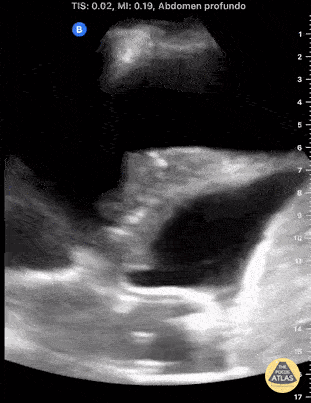

Presence of Anechoic Space with Internal Echoes Dr. Jaime Alejandro Sánchez Gutiérrez Pulmonologist @PLEURALPOCUS